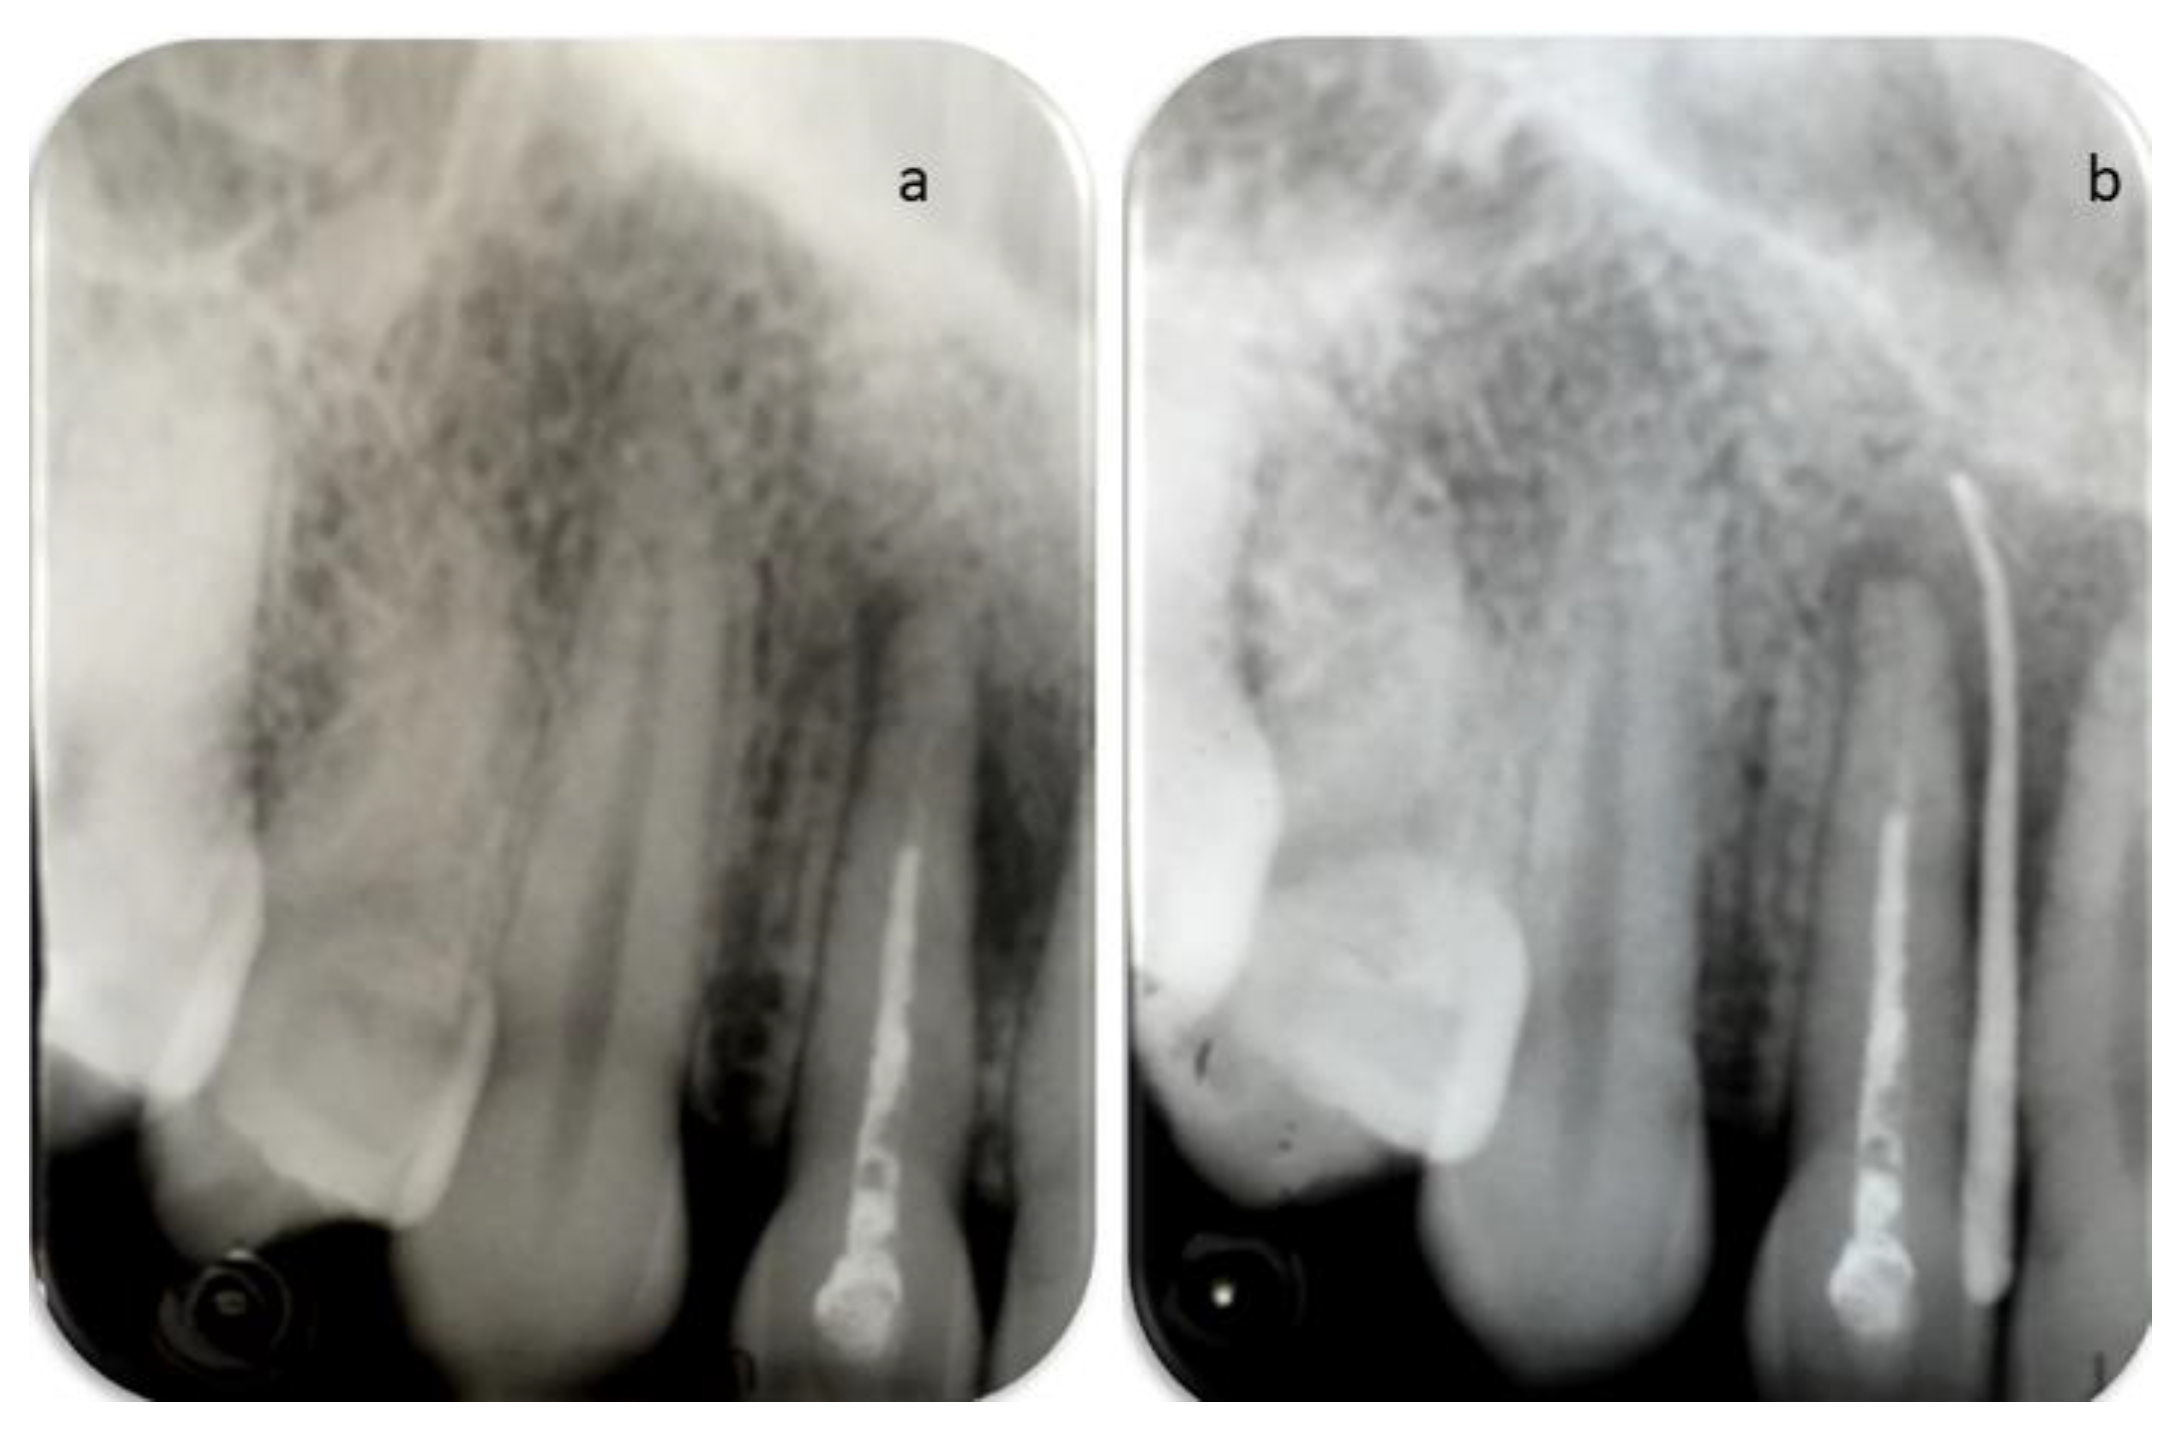

2. Case Report